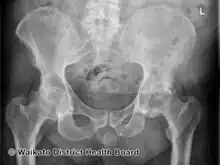

AP Pelvis

Right hand